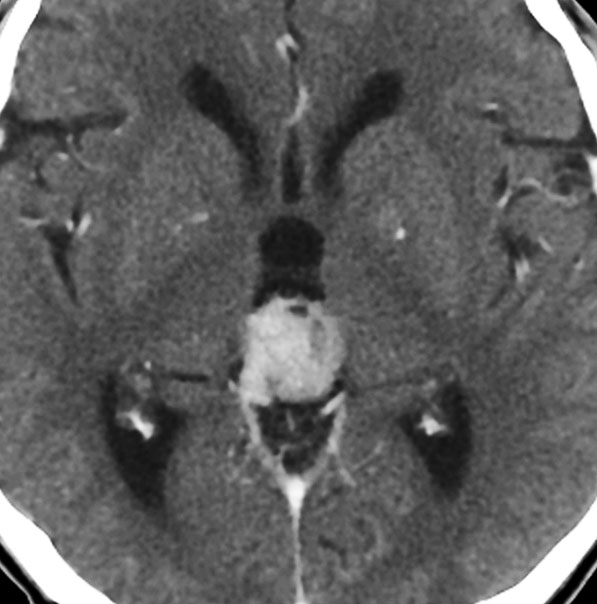

放射線化学療法後の画像です。腫瘍境界は不明瞭(左)で,腫瘍内出血(中央)して,左の視床に浸潤しています。かなりリスクは高いのですが,これを開頭手術で全摘出しました(右),この時点で完全寛解 CR です。この後にさらに化学療法と幹細胞移植(PBSCT,大量化学療法)が加えられました。